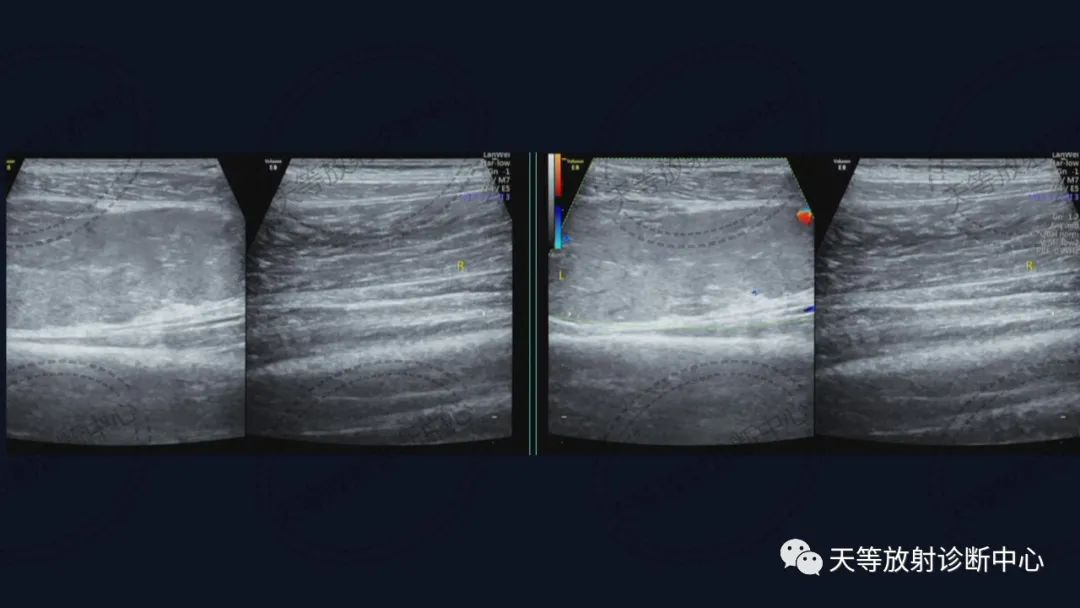

上图:平片显示小腿软组织略肿胀,内部见斑点状钙化灶。